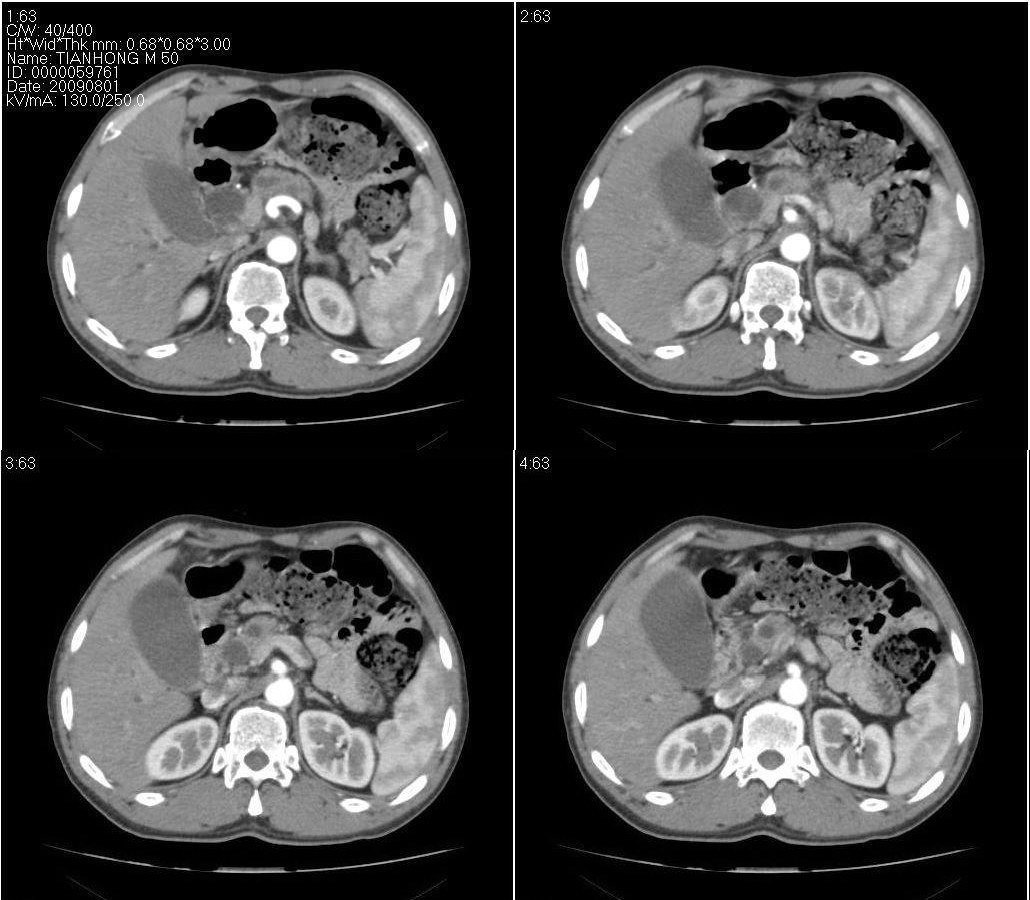

标题: CT21384:男性,50岁。发现无痛性黄疸十余天,B朝提示肝胆管 [打印本页]

标题: CT21384:男性,50岁。发现无痛性黄疸十余天,B朝提示肝胆管

1.考虑:壶腹占位病变(癌?)。

2.胆系低位梗阻:肝内外胆管扩张,胆囊增大,胰管扩张。

胰头癌伴低位胆道梗阻。

胆系低位梗阻(肝内外胆管扩张,胆囊增大,胰管扩张);考虑胰头癌或壶腹癌所致。

胆总管突然中断,壁增厚且强化,考虑胆总管癌可能性大伴胆系梗阻,胆囊炎

胰头强化欠均匀,胆胰管扩张。考虑胰头癌可能性大。

胆系低位梗阻(肝内外胆管扩张,胆囊增大,胰管扩张,钩突似有占位);考虑胰头癌